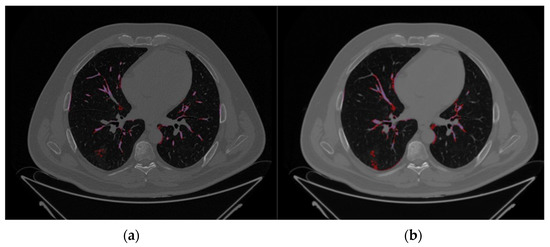

2.2. Image Segmentation and Feature Extraction

3.2. Image Reconstruction and VOI Delineation Results